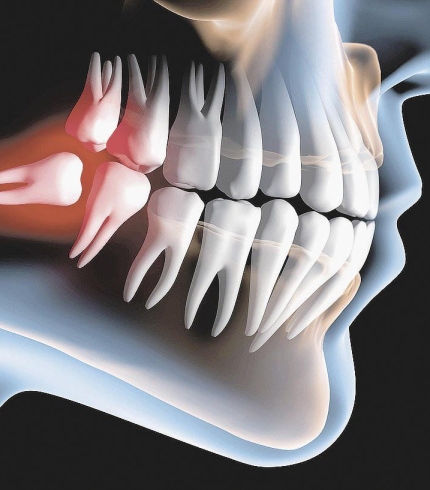

Çene kistleri büyürken herhangi bir klinik bulgu göstermezler ve ağrı yapmazlar. Kist büyüme sonrasında şişlik olarak kendini göstermektedir. Ağrı yapan kistler enfeksiyon belirtisi göstermektedir. Kist büyüdükçe daha büyük sorunların oluşmasına yol açmaktadır. Sinir üzerine baskı yapan kistler alt dudağın uyuşmasına sebep olurken daha da büyüyen kistler dişlerin sallanmasına ya da kendi kendine oluşan çene kırıklarına sebep olabilmektedir. Uzman cerrahi müdahalelerle Çene Kisti Operasyonları başarılı bir şekilde yapılmaktadır. Bu alanda en iyi hizmet veren hekimler arasından bir doktor ekibine sahip İlkdent Diş Kliniğimiz son derece profesyonel ve özenli bir hizmet sunmaktadır.

Çene Kisti Operasyonları yapılırken kist uygulanabiliyorsa tek parça halinde alınmaya çalışılır. Büyük ölçekli kistler önce küçültülür daha sonra cerrahi işlemle alınır. Çene kistleri çene kemiğinde ya da diş köklerinde bulanabilir. Eğer kist diş köklerindeyse operasyon sırasında kist ile ilgili diş ağızda bırakıldıysa dişe kanal tedavisi uygulanır ya da operasyon sırasında diş çekildiyse daha sonra ilgili dişe implant tedavisi uygulanır. Operasyon sonrasında bu süreç hem cerrah hem de hasta tarafından dikkat edilmesi bir dönemdir.